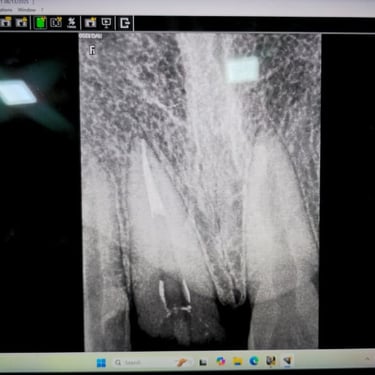

Step 2: Root Canal Treatment (RCT)

RCT was performed to remove the infected pulp and save the natural tooth. This step is crucial to prevent future infection, pain, or tooth loss.

👉 Detailed video explanation :- https://youtube.com/shorts/x368vHjTgpc